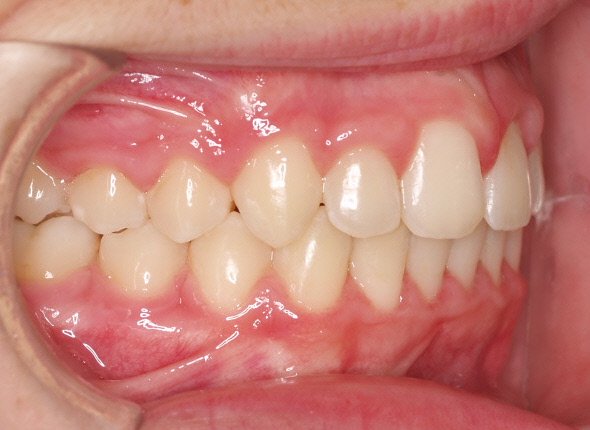

Paciente de 13 años que presenta sonrisa disarmónica.

- Clase I esquelética

- Clase I molar

- DDM +++ anterior

- Sobremordida

Decidimos extraer los 4 primeros premolares.

A los dos años quitamos aparatología fija y la paciente entra en fase de contención encantada con su nueva sonrisa.

Lleva férulas ESSIX a la noche más una contención fija inferior de canino a canino.